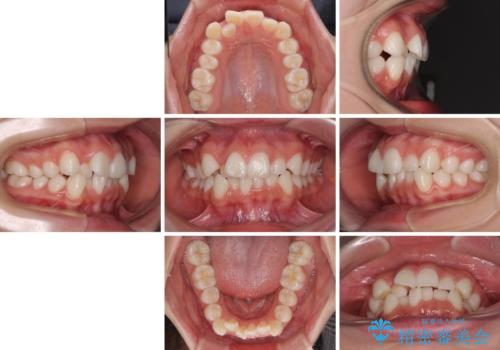

- 歯のデコボコや八重歯、クロスバイトを気にして来院された患者様です。

上下左右第一小臼歯4本を抜歯し、ワイヤー装置にて歯列を整え、さらには少しでも口元を引っ込めるよう矯正治療を行うこととしました。

上下の骨格での左右差が小さかったことと、抜歯矯正であったことで、上下正中の位置をきれいに合わせることができました。